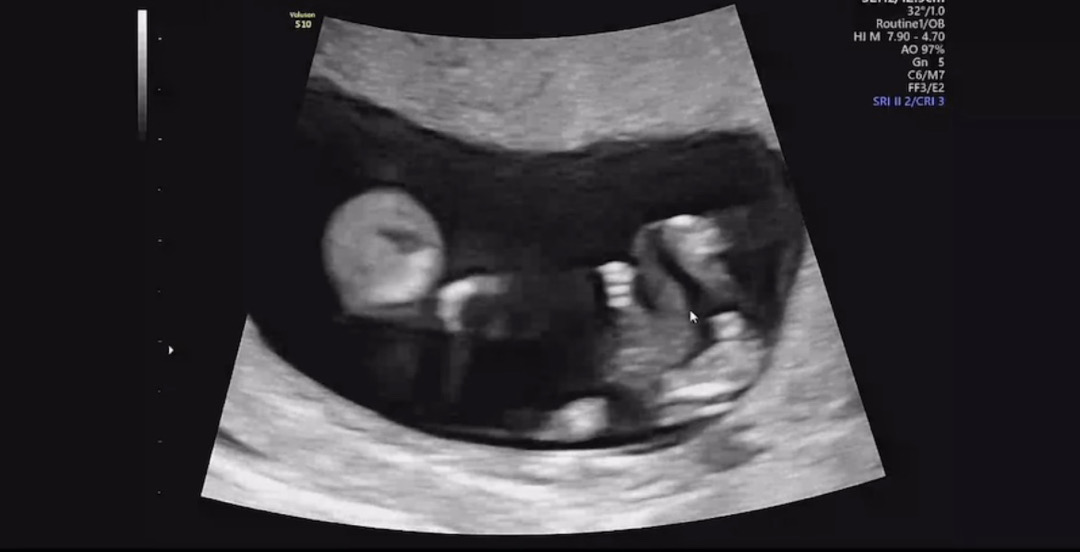

오늘 1차 기형아 검사 받고 초음파 올려보아용 고수님들 한번 봐주세여 ❤거의 정면이에요!! 아빠다리처럼 꼬려고 하는 ..?

정면으로는 알수 없어요ㅎㅎ 측면 척추와 생식기쪽 각도가 나와야해요ㅎㅎ